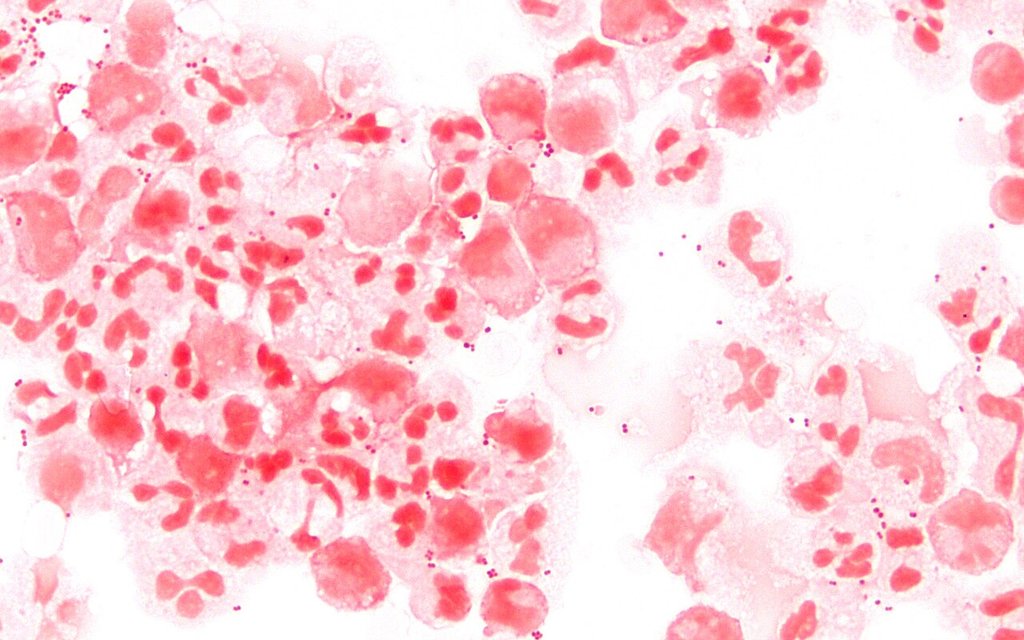

Gram Stain (Mixed Bacteria)

Heat-fixed bacterial smear with Gram staining showing gram-positive and gram-negative organisms

Sputum Gram Stain — Mixed Flora

Gram-stained smear of sputum prepared for microscopic observation showing mixed bacterial morphotypes and inflammatory cells.

gram Downloaded 2026-03-15

Upright Optical

100× Brightfield Focus 0.5 NA 1.25

Oil immersion — positive blood culture, cocci in clusters

Wikimedia Commons — CC BY-SA 3.0